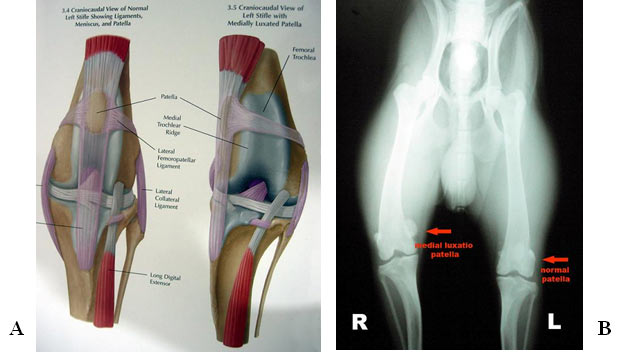

Gambaran patella normal dan luxatio patella.

A.Gambaran skematis patella normal (kiri) dan luxatio patella (kanan) 1.

B.Gambaran radiologi patella normal (patella kiri) dan medial luxatio patella (patella kanan).

Luxatio patella dapat diketahui dari anamnesa, gejala klinis, maupun foto rontgen dari kaki belakang. Klien datang dengan keluhan anjingnya sesekali mengangkat salah satu kaki belakangnya pada waktu berjalan atau berlari. Setelah itu anjing berjalan normal kembali. Dari pemeriksaan klinis dengan palpasi di daerah lutut pada kaki yang pincang terasa adanya pergeseran patella dari lekukan trochlea. Arah bergesernya patella dapat dirasakan ke arah medial (dalam) atau ke arah lateral (luar). Pemeriksaan klinis tersebut dapat diperkuat dengan membuat foto rontgen dari kaki yang diduga bermasalah. Hasil foto rontgen tersebut dapat menunjukkan berapa derajad patella bergeser dari tempatnya. Dari pengalaman praktek, bergesernya patella berkisar antara 30o-60o dari tempatnya. Beberapa kasus dapat bergeser hingga 90o (gambar 1.B) dan satu kasus pernah ditemukan dengan pergeseran 180o (anjing Pomeranian).